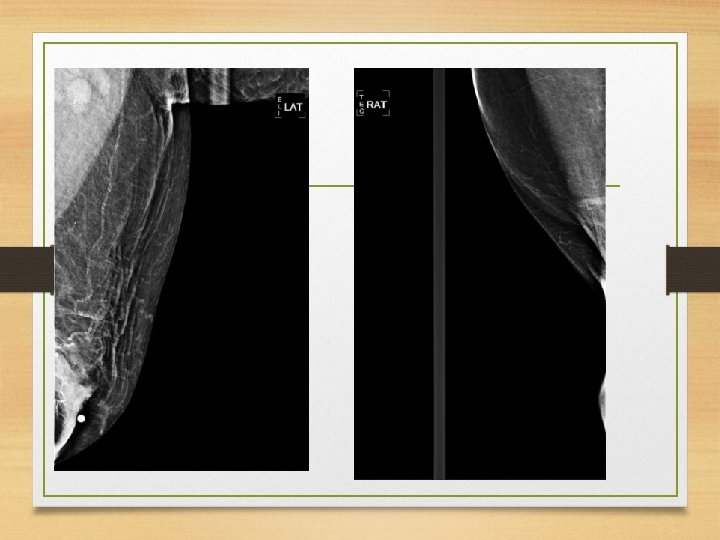

Mediolateral • Útil en patologías en la cara central o lateral de la mama. Para confirmar una anomalía observada en la OML. • • calcificaciones Aire Niveles de liquido Localizar lesiones en plano sagital • Eliminar sobreposiciones • De pie o sentada. • El RC es angulado a 90°.

• La paciente frente al mastografo coloca el brazo del lado a examinar hacia adelante la mano sobre la barra hacia el frente. • Se tracciona la mama y el m. pectoral anterior y medialmente. El pezón de perfil. • Aplicar compresion. • Traccionar el tejido abdominal hacia abajo. • La paciente retrae la mama contralateral con la mano opuesta.

• La imagen debe incluir todo el tejido mamario, • la region axilar y • el m. pectoral.